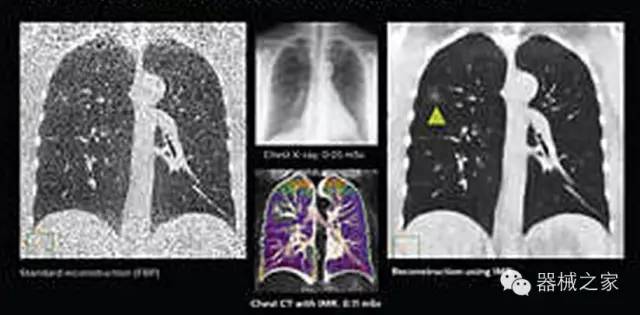

1.低劑量下的胸部顯影

IQon光譜CT能夠按照需求提供光譜量化和工具,并能通過簡單工作流程、在低劑量下對結(jié)構(gòu)進(jìn)行定性分析

IQon光譜CT -- 是業(yè)界首臺以探測器為成像基礎(chǔ)的光譜CT,它可以在單次常規(guī)掃描下獲得傳統(tǒng)解剖影像及光譜功能影像。不僅可以提供精準(zhǔn)的診斷信息,還可簡化工作流程、在低劑量下完成定量與定性分析。